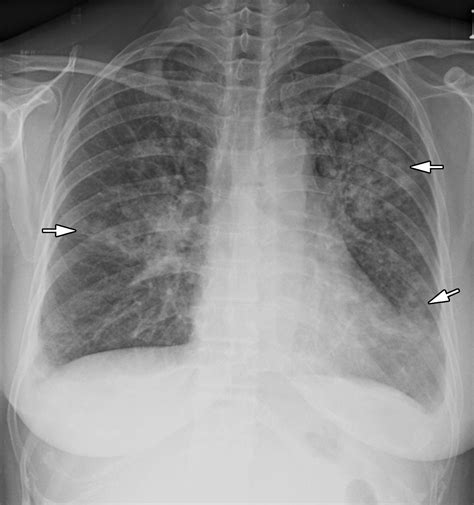

To a radiologist, a healthy lung appears mostly black on an X-ray because it is filled with air, which does not block X-ray beams. However, when pneumonia is present, the affected area of the lung becomes filled with inflammatory fluid and cells. This change in density causes the area to appear as white or grey patches, technically known as “opacities” or “infiltrates.”

• Consolidation: This refers to a solid white area where the air sacs are completely filled with fluid.

• Air Bronchograms: Sometimes, the larger airways remain filled with air, appearing as dark branching lines amidst the white consolidation.

• Patchy Infiltrates: Rather than one solid mass, the pneumonia may appear as scattered, cloudy spots throughout the lung tissue.